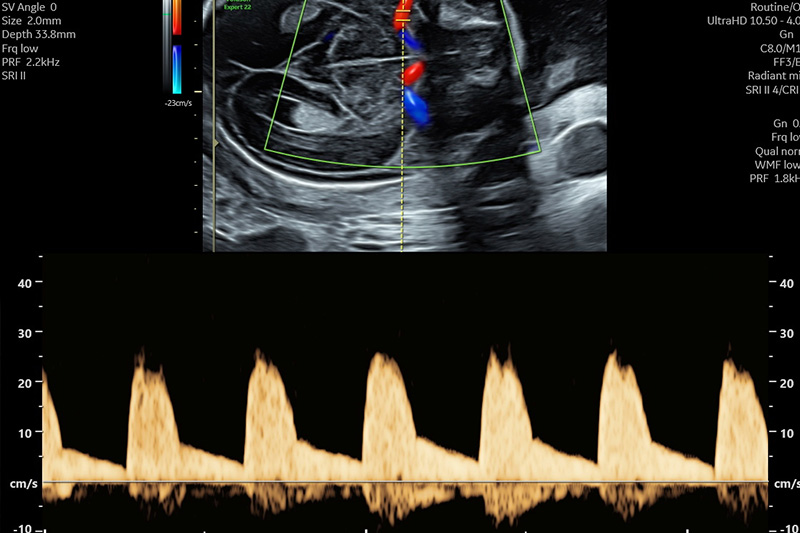

Die Dopplersonografie ist eine Untersuchung in der die Gefäße des Kindes, der Placenta und der Gebärmutter beurteilt werden. Insbesondere der Strömungswiderstand und die Blutflussgeschwindigkeiten

geben Aufschluss über eventuelle Risikokonstellationen und können in Fällen von kindlicher Wachstumshemmung den optimalen Geburtszeitpunkt für das Kind bestimmen.

Es ist möglich mittels Screening eine kindliche Wachstumshemmung und die Entwicklung einer Präeklampsie („Schwangerschaftsvergiftung“) abzuschätzen und die weitere Schwangerschaftsbetreuung individueller anzupassen.